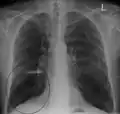

A chest X-ray is not useful to establish a diagnosis of COPD, but it is of use in either excluding other conditions or including comorbidities such as pulmonary fibrosis and bronchiectasis. Characteristic signs of COPD on X-ray include hyperinflation (shown by a flattened diaphragm and an increased retrosternal air space) and lung hyperlucency.[5] A saber-sheath trachea may also be shown that is indicative of COPD.[111]

Lung bulla as seen on chest X-ray in a person with severe COPD